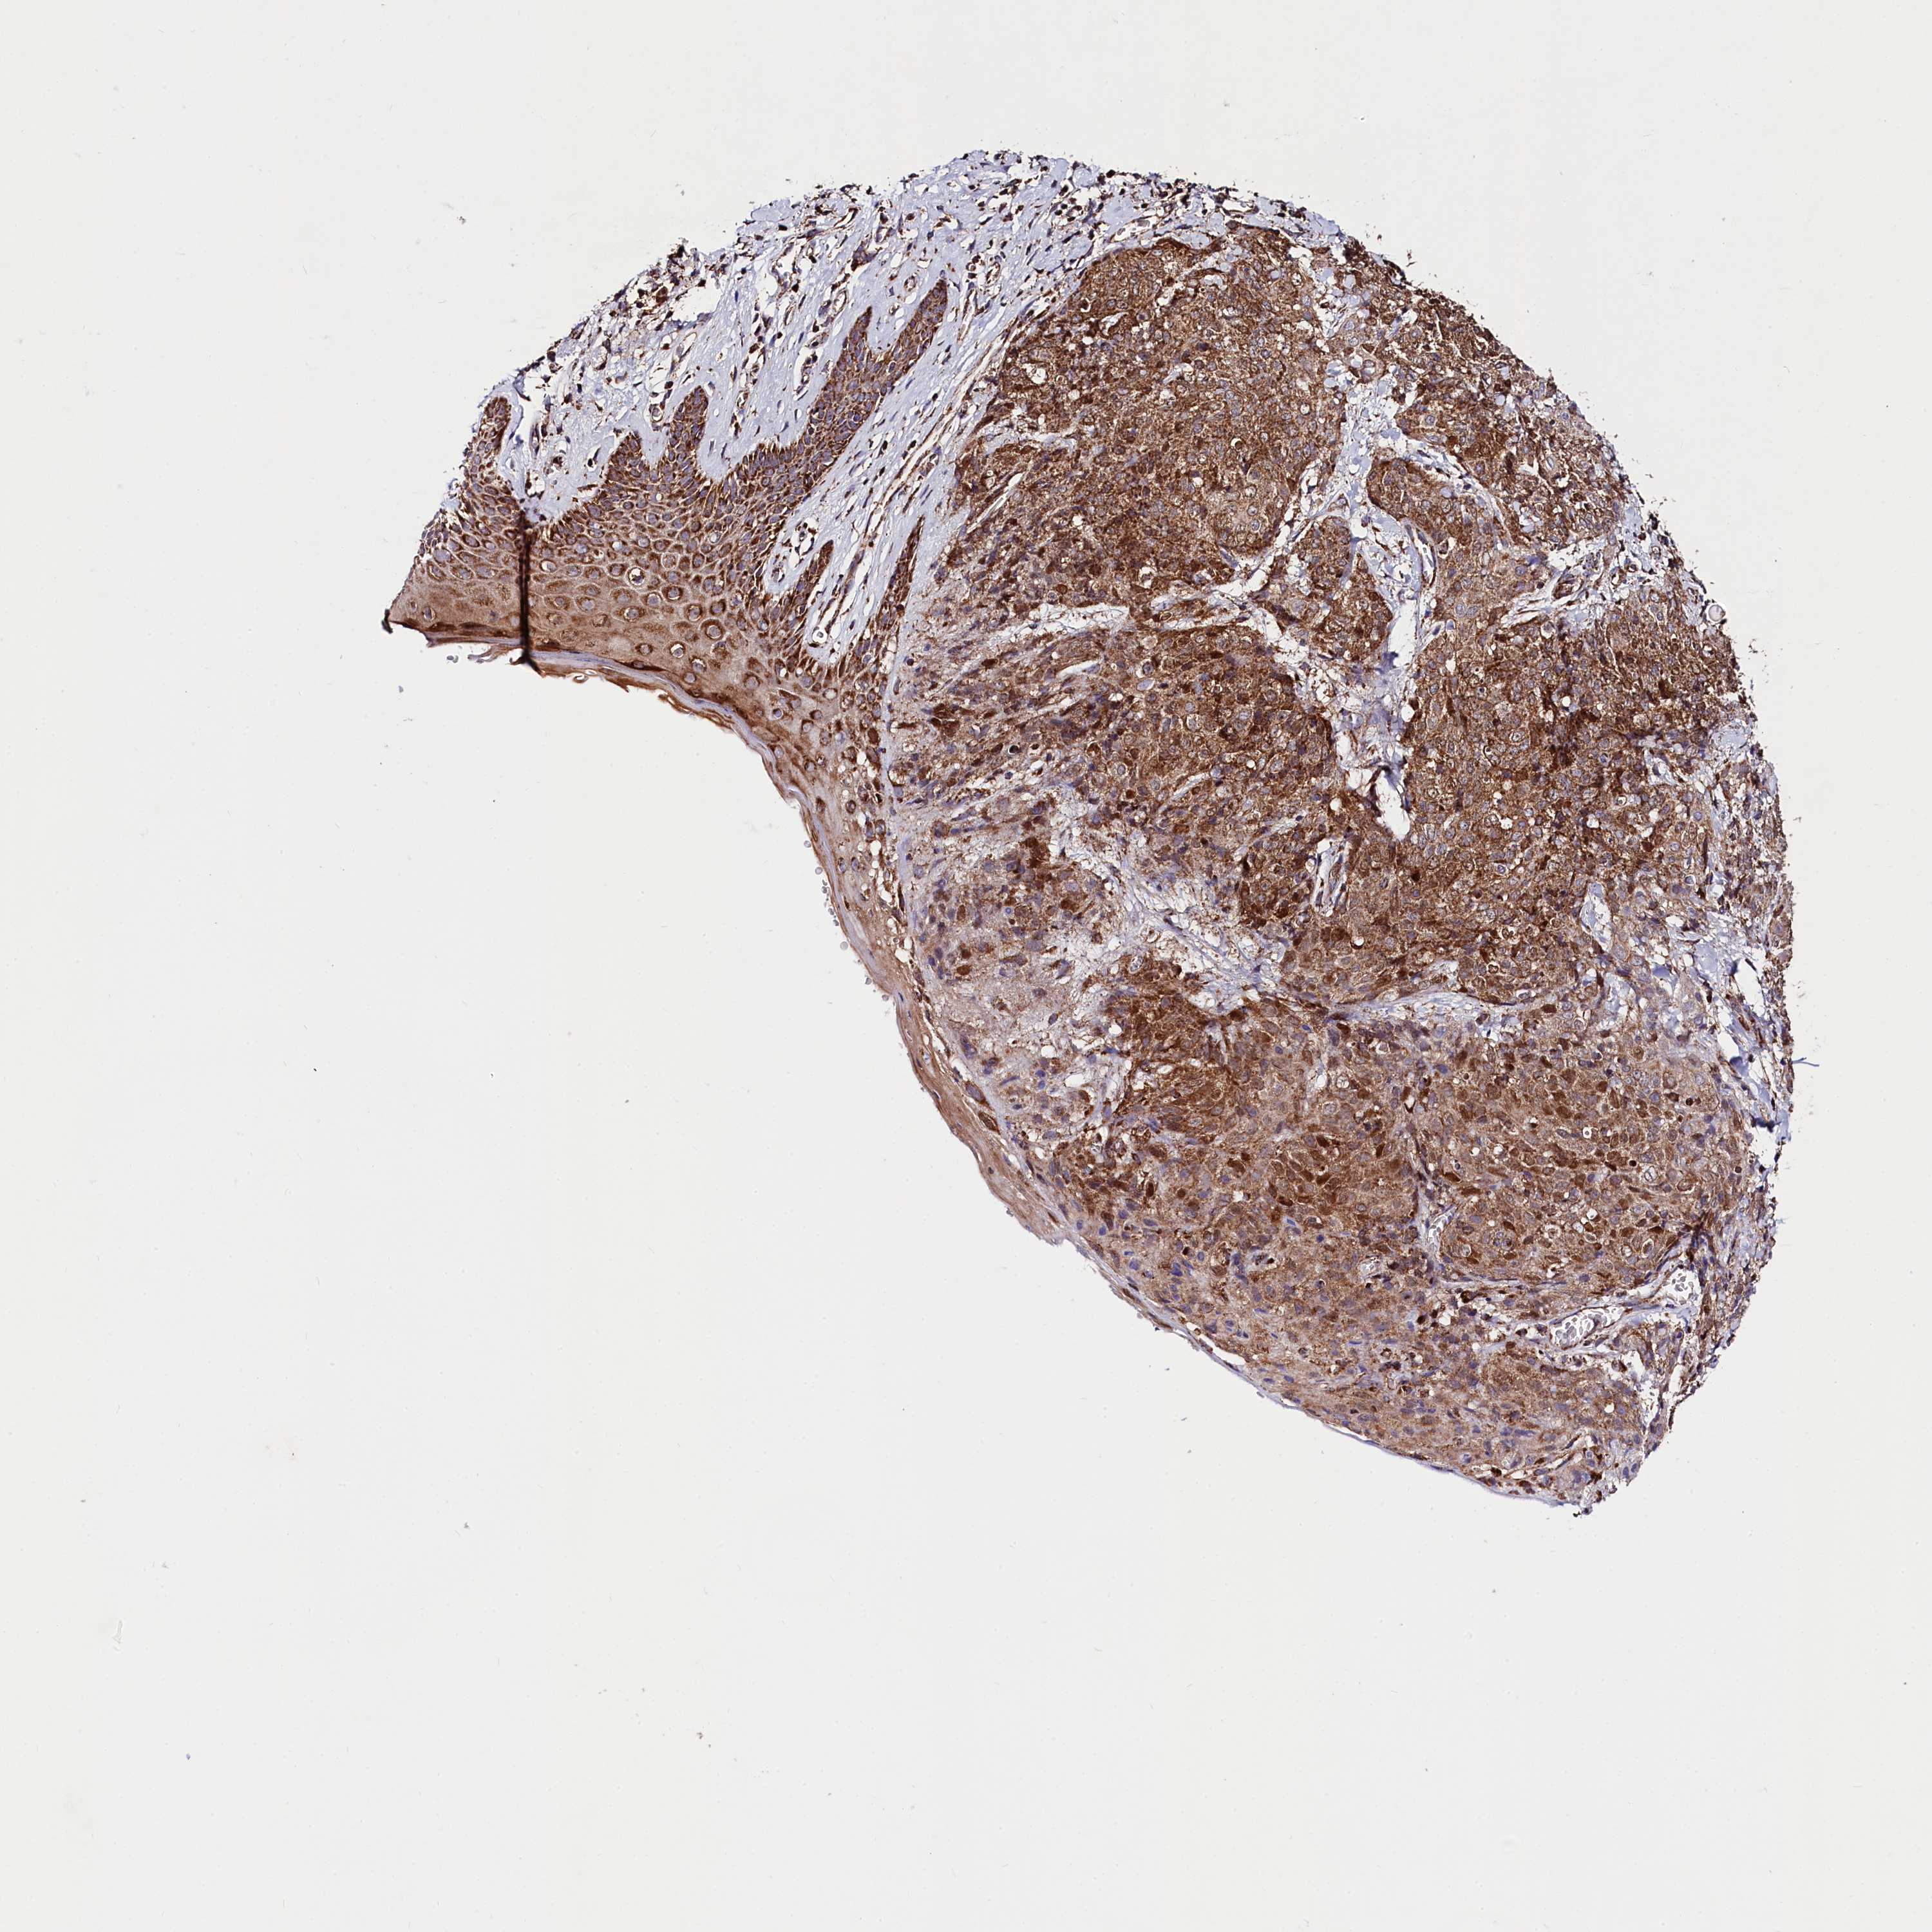

SKIN CANCER - Protein expressioni

A mouse-over function shows sample information and annotation data. Click on an image to view it in a full screen mode. Samples can be filtered based on level of antibody staining by selecting one or several of the following categories: high, medium, low and not detected. The assay and annotation is described here.

Each image is clickable and will lead to virtual microscopy that enables deeper exploration of all samples and also displays staining intensity scores, fraction scores and subcellular localization as well as patient and tissue information for each sample.

Antibody HPA039959

Staining

High

Location

Cytoplasmic/membranous

Basal cell carcinoma